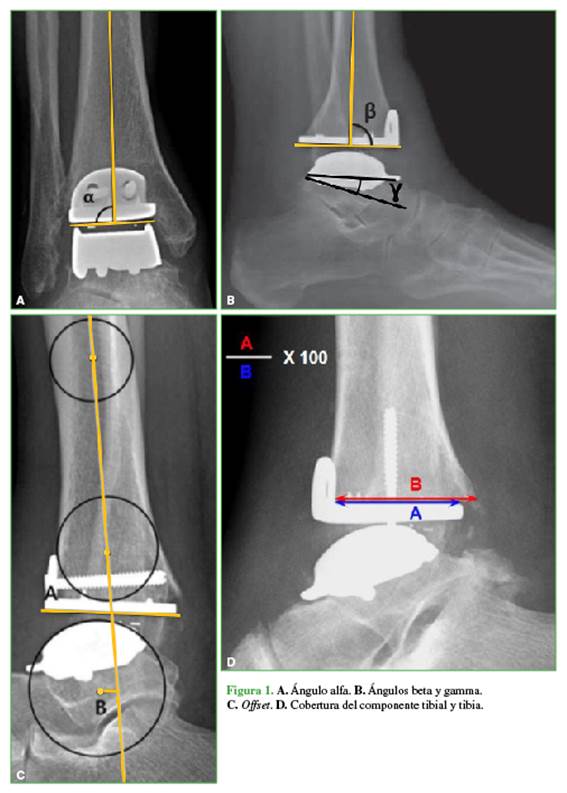

Para estudiar la alineación de la prótesis en el plano frontal se tomó el ángulo alfa6 (varo: >92, valgo: <86)7 y la inclinación tibial en la radiografía de perfil con el ángulo beta6. Se definió como valor positivo <86° y como negativo una disminución (>92°).7

La posición del centro de rotación del astrágalo, offset de la prótesis, se evaluó en relación con el eje longitudinal de la tibia en la proyección lateral,8 se puede ubicar por delante del eje de la tibia (positivo), por detrás (negativo) o centrado (neutro) (Figura 1).

Se analizó también la relación de tamaño entre el componente tibial de la prótesis y la tibia utilizando una adaptación que hemos desarrollado para la prótesis Hintegra® basándonos en aquellas realizadas por otros autores,3,5,9 con el fin de poder cuantificar el grado de cobertura o falta de cobertura posterior.

La relación entre el tamaño de la tibia y el componente tibial de la prótesis (cobertura) se evaluó en la radiografía de perfil del posoperatorio inmediato. Se trazaron dos líneas paralelas al componente tibial, desde el borde posterior del muro anterior del componente tibial hasta el borde posterior de este (línea A) y otra línea hasta la cortical posterior de la línea tibial (línea B). Sobre la base de ambas líneas, se midió la relación (línea A/línea B x 100), que da como resultado el porcentaje de cobertura. Se considera 100% cuando ambos bordes de la tibia y del componente tibial están alineados en el eje vertical. Se considera sobrecobertura a más del 100% (sobresale la prótesis hacia posterior) y falta de cobertura a menos del 100% (sobresale la tibia hacia posterior).